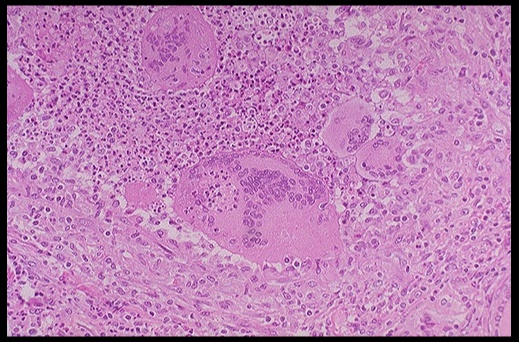

_On histology, a lymphocytic infiltrate with multinucleated giant cells surround fragments of colloid.

.,Subacute granulomatous thyroiditis. Note the giant cells, inflammatory cells and destruction of the thyroid follicules.

_The treatment is aspirin. In severe disease, cortisol may supplement this treatment. Thyroid symptoms is mild and resolve in a few weeks.,